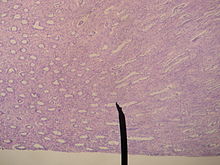

Histology

Renal histology studies the structure of the kidney as viewed under a microscope. Various distinct cell types occur in the kidney, including:

Renal Biopsy

The role of the renal biopsy is to diagnose renal disease in which the etiology is not clear based upon noninvasive means (clinical history, past medical history, medication history, physical exam, laboratory studies, imaging studies).

A detailed description of renal biopsy interpretation is beyond the scope of this article. In general- a renal pathologist will perform a detailed morphologic evaluation and integrate the morphologic findings with the clinical history and laboratory data, ultimately arriving at a pathologic diagnosis. A renal pathologist is a physician who has undergone general training in anatomic pathology and additional specially training in the interpretation of renal biopsy specimens.

Ideally, multiple core sections are obtained and evaluated for adequacy (presence of glomeruli) intraoperatively. A pathologist/pathology assistant divides the specimen(s) for submission for light microscopy, immunofluorescence microscopy and electron microscopy.

The pathologist will examine the specimen using light microscopy with multiple staining techniques (hematoxylin and eosin/H&E, PAS, trichrome, silver stain) on multiple level sections. Multiple immunofluorescence stains are performed to evaluate for antibody, protein and complement deposition. Finally, ultrastructural examination is performed with electron microscopy and may reveal the presence of electron-dense deposits or other characteristic abnormalities which may suggest an etiology for the patient's renal disease.